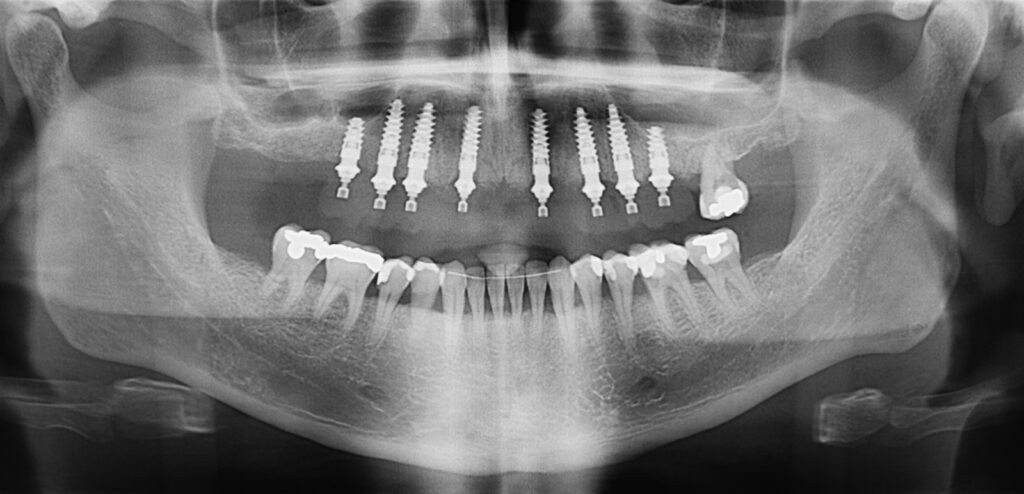

Caso clínico, Dr. José Amador Cabezas

Carga inmediata maxilar con cirugía guiada, registro fotogramétrico y provisionalización inmediata.

En este caso, el Dr. José Amador Cabezas aborda la rehabilitación completa de un maxilar superior comprometido por enfermedad periodontal avanzada, lesiones periapicales y múltiples restauraciones fallidas.

Tras la planificación protésicamente guiada y la colocación de implantes mediante cirugía guiada, se realizó el registro fotogramétrico con T-Marker sobre los Multi-Unit para capturar con precisión la posición real de los implantes y asegurar la pasividad de la estructura provisional.

Gracias a este flujo, el paciente pudo salir de la consulta con una prótesis fija inmediata el mismo día de la cirugía, iniciando así un proceso restaurador más preciso, más predecible y completamente integrado en el entorno digital.

La combinación de cirugía guiada, fotogrametría y carga inmediata permite un control preciso de la posición implantaria y una correcta pasividad protésica desde el primer día.